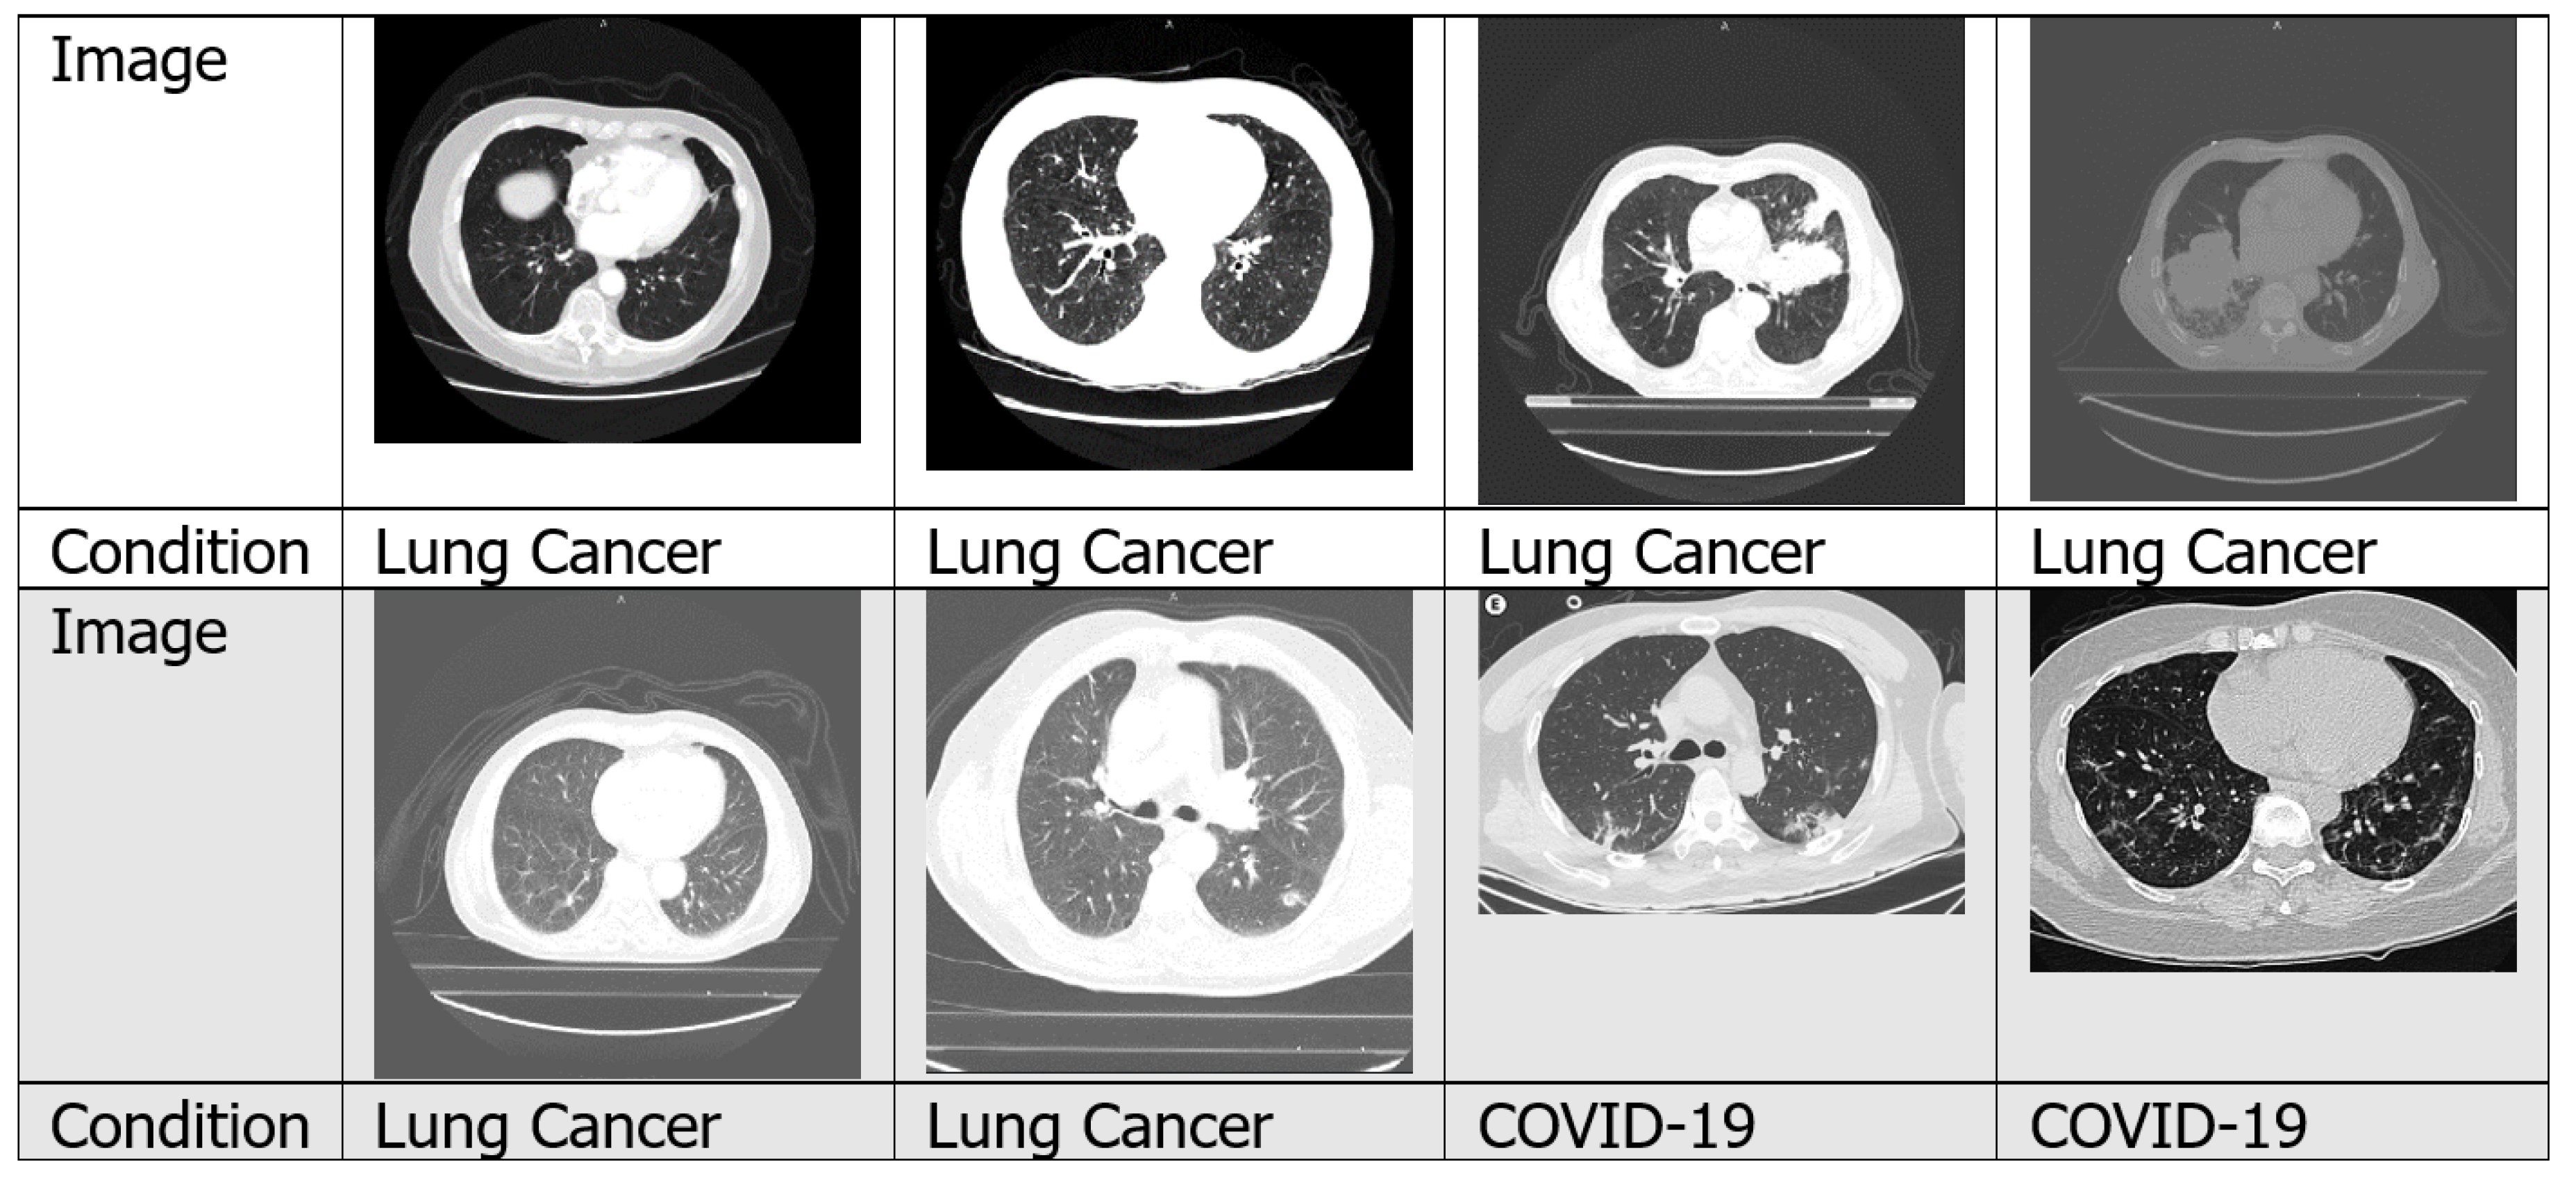

4.1.2. CT Scans

4.7.3. Lung Cancer

4.7.4. COVID-19